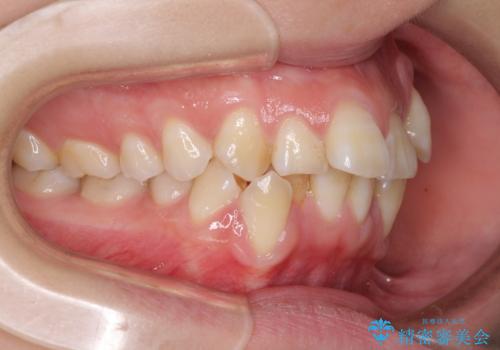

- 上下前歯の叢生と八重歯を気にして来院された患者様です。

前歯部叢生のスペースを獲得するため、上下顎左右小臼歯各1歯を抜歯することとしました。